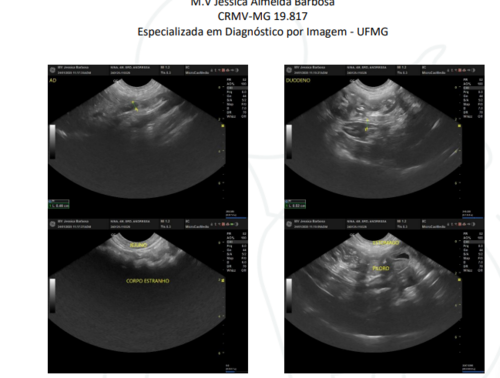

Dia 23 de janeiro, a Nina pegou uma meia de algodão e engoliu, precisando agora passar por uma cirurgia urgente. Não temos o valor para pagar a cirurgia, quem ama pets como nós e puder ajudar a salvar a Nina.